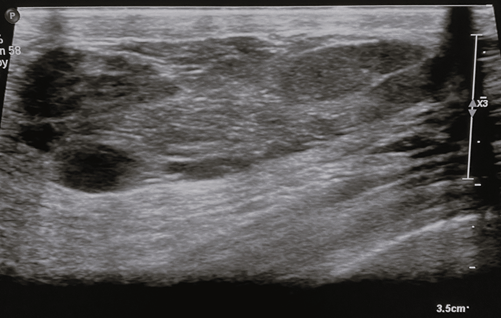

Ultrasound

On ultrasound, the appearance of MH differs widely owing to the marked variability in the fatty and fibrous tissue constituents. They generally appear as solid, well-circumscribed, oval formations with heterogeneous echogenicity [24], aligned parallel to the skin plane (Figure 3). The lesion typically lacks hypervascularization on colour Doppler imaging and shows an echogenic or echolucent halo with posterior strengthening [2]. Incomplete pseudocapsule and tiny size with minimal fat content might make diagnosis challenging [8].

Figure 3. Breast ultrasound – breast ultrasound shows a tissue formation with the long axis parallel to the cutaneous plane, well-circumscribed, heterogeneous, with hypoechoic with hyperechoic trabeculae and posterior acoustic enhancement. Image credits: El Yousfi Z, El Mansoury FZ, El Bakkari A, Omor Y, Latib R. Breast hamartoma with synchronous contralateral breast cancer: a case report. Cureus 2024; 16(8): e66534. DOI: 10.7759/cureus.66534. Reused under the terms of the Creative Commons Attribution License CC-BY 4.0. (https://creativecommons.org/licenses/by/4.0/deed.en).